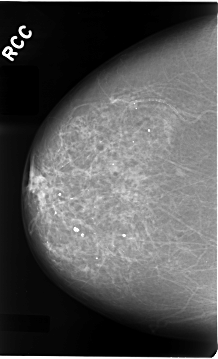

Volume: cancer_02 Case: C-0028-1

C_0028_1.RIGHT_CC

RIGHT_CC LINES 4664 PIXELS_PER_LINE 2832 BITS_PER_PIXEL 12 RESOLUTION 50 NON_OVERLAY